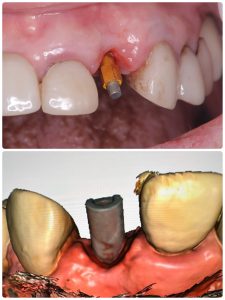

画像は全てメタルプレート、クリアランスが少ない

ジルコニア生活歯バイオコーティングし圧排しながらスキャン サンメディカル社は素晴らしい

オペ後6から7wでの22番インプラント印象

ISQ75全周